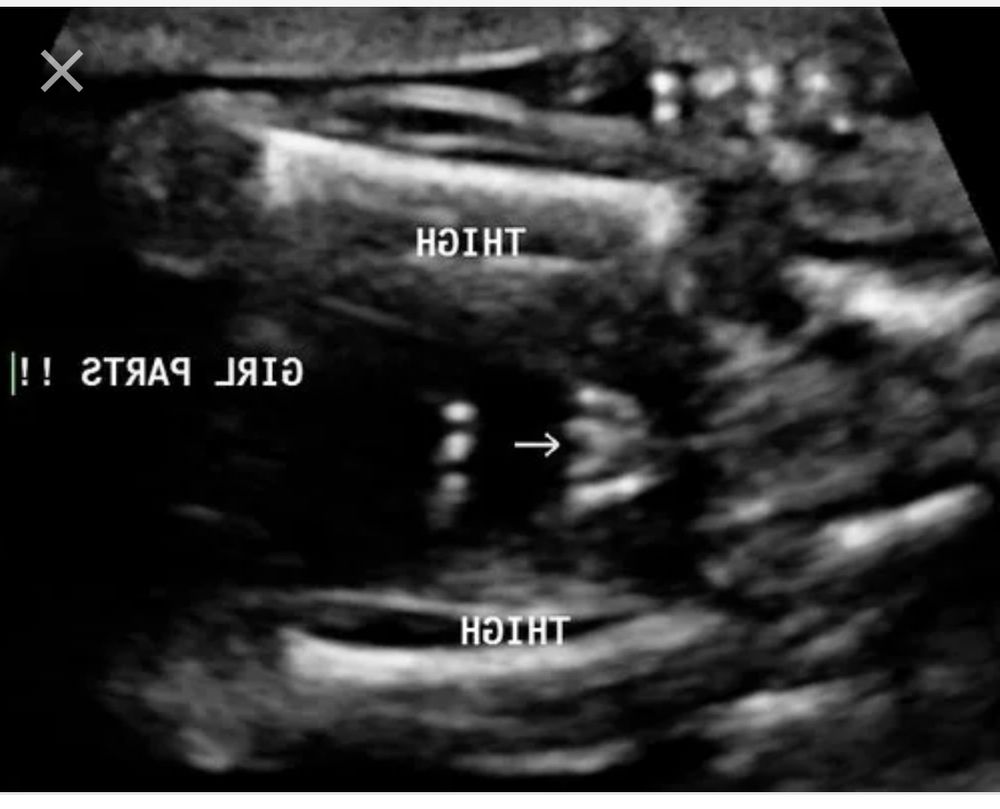

Лилия, потерпите до 2 скрининга )))но в 16 думаю уже увидели вашу доченьку . У нас прям кофейное зернышко было между ножек

Нам в 14 недель сказали мальчик 98%, в 17 недель стала девочка , в 20 тоже девочка и родилась девочка